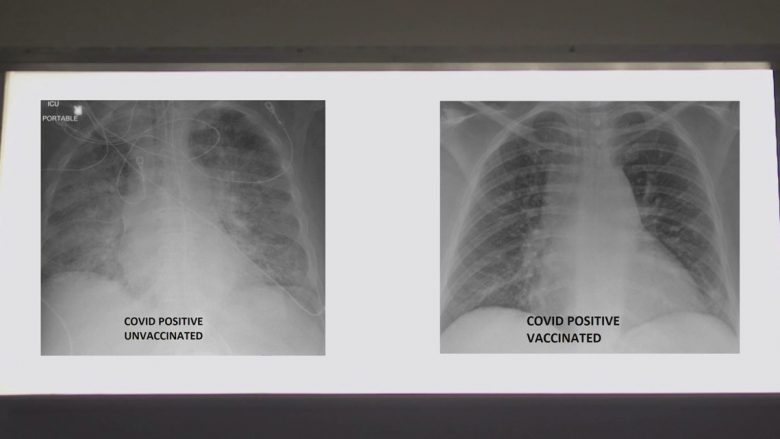

Dr. Kamel ka publikuar rëntgenin e mushkërive të dy pacientëve me coronavirus, por që njëri prej tyre e ka marrë vaksinën dhe tjetri jo, me qëllim për ta dëshmuar efikasitetin e vaksinës kundër COVID-19.

Në ekzaminimin e rëntgeneve, ai tregon se ngjyra e bardhë në mushkri shfaq përhapjen e virusit, e që sipas tij mund të jenë baktere, mukozë apo sekrecion.

“Nëse shikoni mushkëritë e pacientit të vaksinuar, do të shihni që ato janë plotë oksigjen dhe duken të zeza – apo më mirë thënë dominon ngjyra e zezë sesa e bardha, siç ishte rasti me pacientin me COVID-19, por që nuk është vaksinuar.”